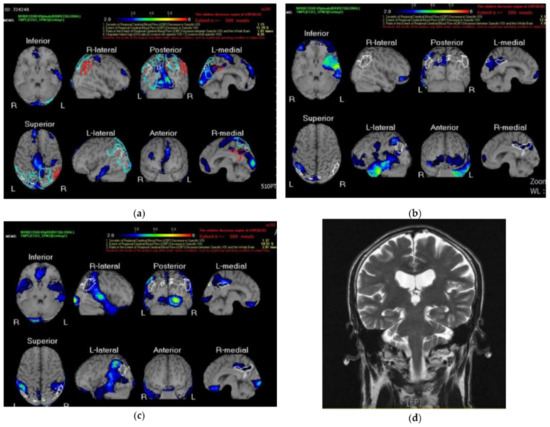

- Varma, A.R.; Adams, W.; Lloyd, J.J.; Carson, K.J.; Snowden, J.S.; Testa, H.J.; Jackson, A.; Neary, D. Diagnostic patterns of regional atrophy on MRI and regional cerebral blood flow change on SPECT in young onset patients with Alzheimer’s disease, frontotemporal dementia and vascular dementia. Acta Neurol. Scand. 2002, 105, 261–269. [Google Scholar] [CrossRef]

- Valotassiou, V.; Malamitsi, J.; Papatriantafyllou, J.; Dardiotis, E.; Tsougos, I.; Psimadis, D.; Alexiou, S.; Hadjigeorgiou, G.; Georgoulias, P. SPECT and PET imaging in Alzheimer’s disease. Ann. Nucl. Med. 2018, 32, 583–593. [Google Scholar] [CrossRef]

- Valotassiou, V.; Angelidis, G.; Psimadas, D.; Tsougos, I.; Georgoulias, P. In the era of FDG PET, is it time for brain perfusion SPECT to gain a place in Alzheimer’s disease imaging biomarkers? Eur. J. Nucl. Med. Mol. Imaging 2021, 48, 969–971. [Google Scholar] [CrossRef]

- Hashimoto, H.; Nakanishi, R.; Mizumura, S.; Hashimoto, Y.; Okamura, Y.; Yamanaka, K.; Ikeda, T. Prognostic value of 99mTc-ECD brain perfusion SPECT in patients with atrial fibrillation and dementia. EJNMMI Res. 2020, 10, 3. [Google Scholar] [CrossRef]

- Davison, C.M.; O’Brien, J.T. A comparison of FDG-PET and blood flow SPECT in the diagnosis of neurodegenerative dementias: A systematic review. Int. J. Geriatr. Psychiatry 2014, 29, 551–561. [Google Scholar] [CrossRef]

- Baker, J.G.; Williams, A.J.; Wack, D.S.; Miletich, R.S. Correlation of Cognition and SPECT Perfusion: Easy Z Score and SPM Analysis of a Pilot Sample with Cerebral Small Vessel Disease. Dement. Gediatr.Cogn. Dis. 2013, 36, 290–299. [Google Scholar] [CrossRef]